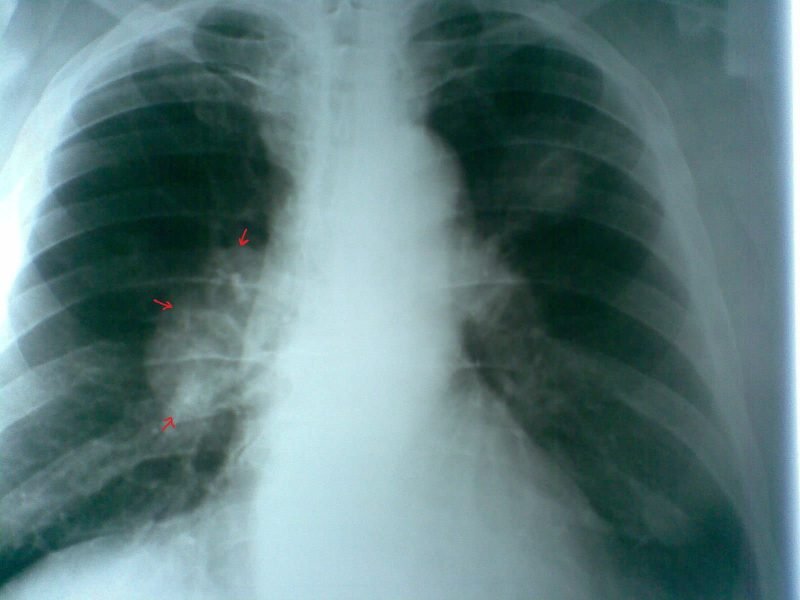

В то же время быстро и легко выявить онкологию легких с помощью флюорографии удается не всегда. Поставить диагноз получается при достижении карциномой внушительных размеров и в том случае, если на снимке хорошо видно новообразование. Обычно это происходит при достижении опухоли легких последней стадии либо при нахождении человека в тяжелом состоянии, которое сопровождается развитием множества осложнений. При незначительном затемнении на флюорографическом снимке для подтверждения диагноза назначаются дополнительные исследования.

Флюорография может не показать злокачественное новообразование в легких и в том случае, если оно локализуется на поверхности, а не в глубине. При таком патологическом состоянии органа специалист назначает пациенту проведение рентгена, компьютерной либо магнитно-резонансной томографии, показывающие, как выглядит проблемная зона.

Такой метод исследования, как флюорография, может показать в легких, скопление в них жидкости и наличие очагов инфекционных поражений. Кроме этого, такой метод диагностики позволяет рассмотреть корни бронхов и легких, которые при различных патологиях могут быть уплотнены либо расширены.